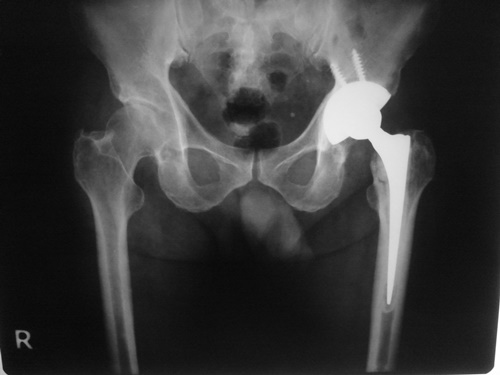

แนวทางการรักษากระดูกสะโพกหักในปัจจุบันที่ดีและเหมาะสมที่สุด คือ การรักษาด้วยการผ่าตัด จากงานวิจัยของคณะแพทยศาสตร์ มหาวิทยาลัยเชียงใหม่ และโรงพยาบาลมหาราชนครราชสีมาพบว่า การรักษาผู้ป่วยด้วยวิธีการไม่ผ่าตัด นอนดึงให้กระดูกติด จะทำให้ผู้ป่วยมีโอกาสเสียชีวิตมากกว่าผู้ป่วยในกลุ่มที่รักษาด้วยการผ่าตัดมากถึง 2 – 3 เท่า ดังนั้น การรักษาผู้ป่วยกระดูกสะโพกหักอันเนื่องมาจากโรคกระดูกพรุนด้วยการผ่าตัดจะช่วยรักษาให้ผู้ป่วยสามารถลุกเดิน เคลื่อนไหวได้ไวขึ้น มีการเกิดโรคแทรกซ้อนน้อย และช่วยลดอัตราการเสียชีวิตลงได้ การผ่าตัดส่วนใหญ่นั้นขึ้นอยู่กับตำแหน่งการหักของกระดูกสะโพก บางครั้งก็ใช้วิธีการผ่าตัดยึดตรึงกระดูกด้วยแผ่นเหล็ก บางครั้งก็ผ่าตัดเปลี่ยนข้อสะโพกเทียม